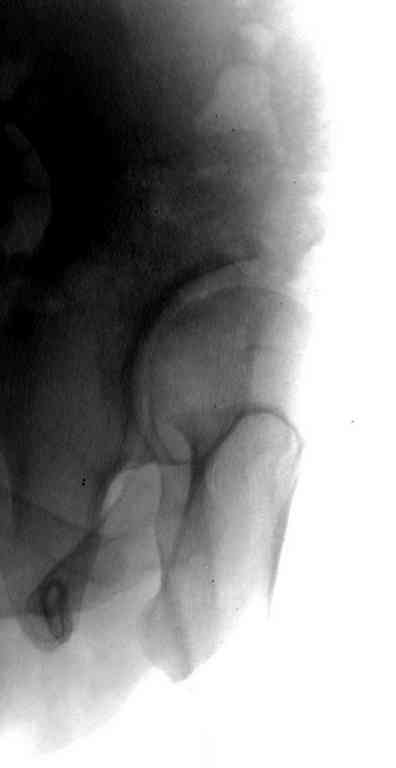

Данный сустав в начальной стадии разрушения, но все-таки я бы сделал обзорный таз и отдельные снимки сустава в 30 градусной абдукции и аддукции. Также снимки с внутренней и наружной ротацией для оценки состояния головки бедра.